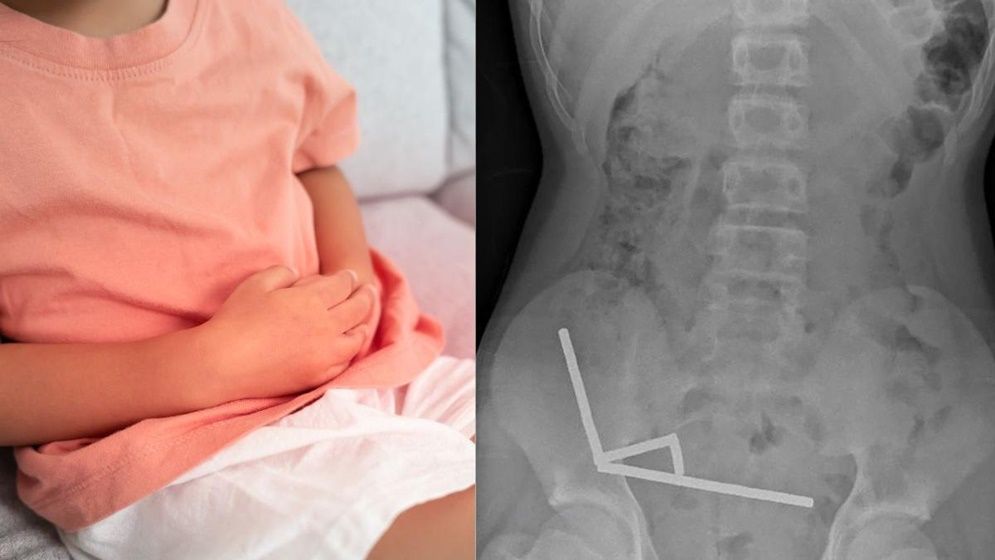

নিউজিল্যান্ডে ১৩ বছর বয়সি এক কিশোরের পেট থেকে প্রায় ১০০টি শক্তিশালী চুম্বক অপসারণ করা হয়েছে। এই ঘটনা ঘটেছে নর্থ আইল্যান্ডের টরাঙ্গা হাসপাতালে, যেখানে চার দিন ধরে পেটে তীব্র ব্যথা নিয়ে কিশোরটিকে ভর্তি করা হয়। চিকিৎসকদের মতে, কিশোরটি ভর্তির প্রায় এক সপ্তাহ আগে ৮০ থেকে ১০০টি নিওডিমিয়াম চুম্বক গিলে ফেলেছিল, যার আকার ছিল ৫ x ২ মিলিমিটার। এক্স-রে রিপোর্টে দেখা যায়, চুম্বকগুলো তার অন্ত্রের ভেতরে চারটি সরলরেখায় জড়ো হয়ে গিয়ে অন্ত্রের বিভিন্ন অংশকে একসঙ্গে আটকে দিয়েছে।

চুম্বকীয় শক্তির কারণে অন্ত্রের কিছু অংশে তীব্র চাপ সৃষ্টি হয়েছিল, ফলে টিস্যু নষ্ট হয়ে গিয়েছিল। জরুরি অস্ত্রোপচারের মাধ্যমে সার্জনরা মৃত টিস্যু অপসারণ করে আটকে থাকা চুম্বকগুলো বের করেছেন। কিশোরটির ক্ষুদ্রান্ত্র এবং বৃহদন্ত্রের চারটি স্থানে টিস্যু মারা গিয়েছিল। আট দিনের হাসপাতালে থাকার পর তাকে ছাড়পত্র দেওয়া হয়েছে।